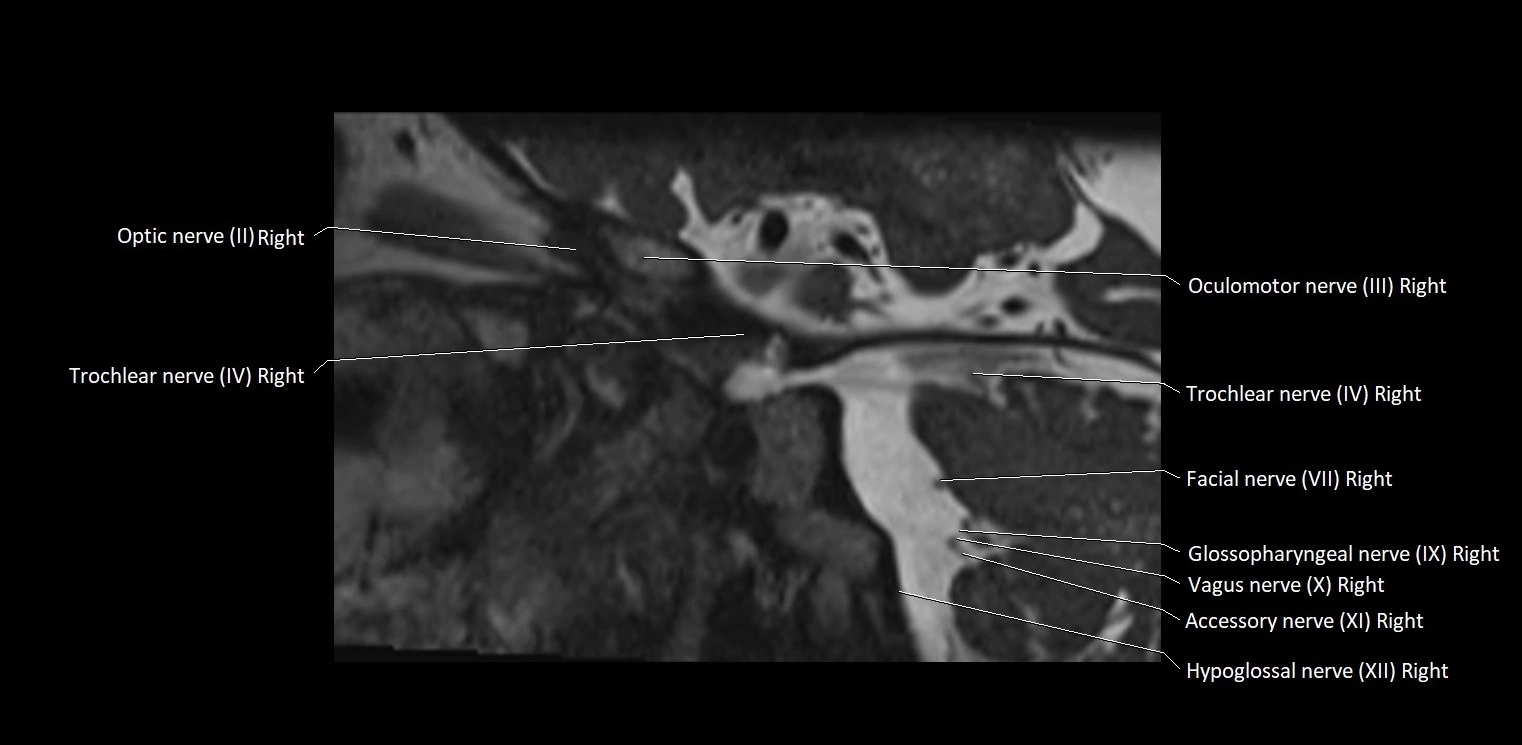

MRI Appearance

• The abducens nerve is a small, thin, linear structure

• Best visualized on high-resolution T2-weighted 3D MRI sequences (e.g., FIESTA or CISS)

• Seen as a hypointense (dark) line running from the brainstem at the pontomedullary junction, traversing the prepontine cistern, and entering Dorello’s canal under the petrosphenoidal ligament, then into the cavernous sinus, and finally the orbit

• May be challenging to visualize in standard MRI due to its small size

• Pathology may be inferred by absence, displacement, or enhancement of the nerve

MRI images

image